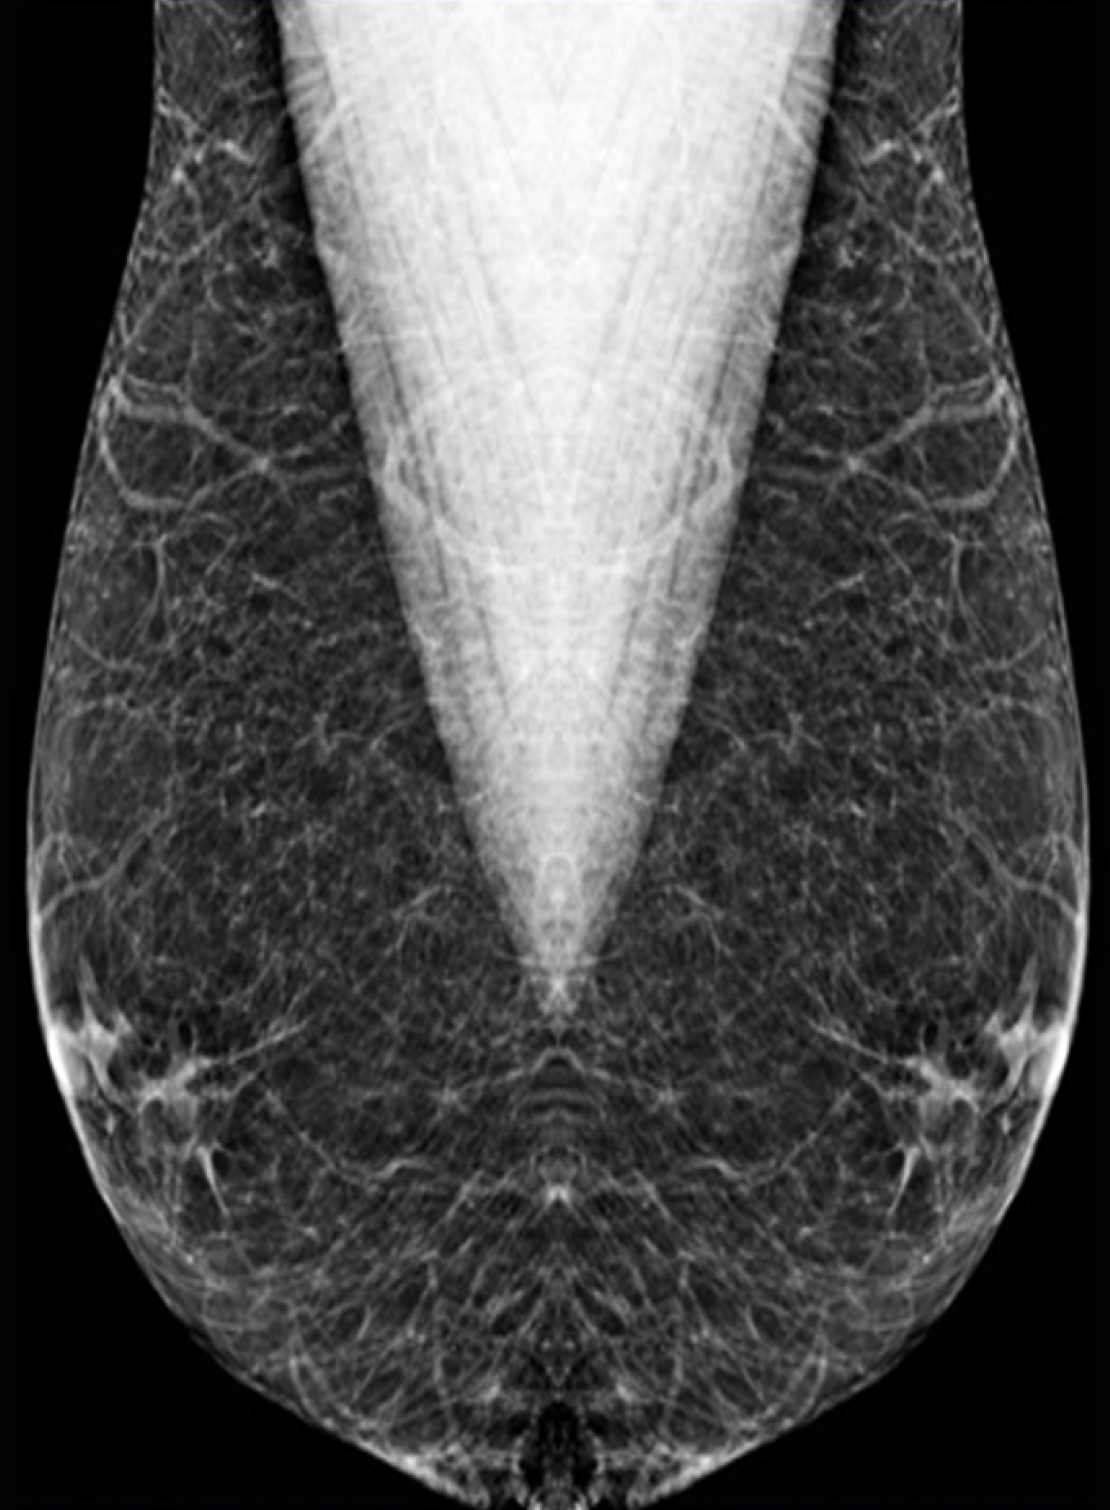

Figure 3

Pseudogynecomastia: Mediolateral oblique mammography view of a 17-year-old obese male showing a diffuse bilateral increase in fat density.